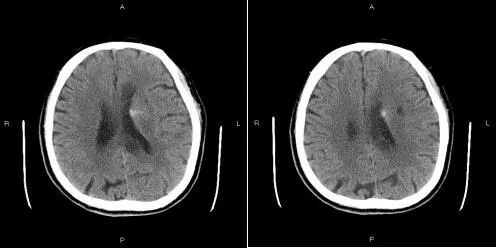

患者术前颅脑DWI:

1.急性脑梗塞

2.左侧大脑中动脉狭窄

3.右侧椎动脉V4段狭窄